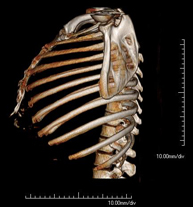

- TC Parrilla costal Exploración radiológica que mediante un sistema de rayos X y detectores que giran alrededor del paciente, reconstruyendo las imágenes por ordenador, permite el estudio detallado de la parrilla costal. Exploración radiológica que mediante un sistema de rayos X y detectores que giran alrededor del paciente, reconstruyendo las imágenes por ordenador, permite el estudio detallado de la parrilla costal.

- Tórax- TC Tórax Prueba diagnóstica que consiste en obtener imágenes del tórax de alta definición anatómica (pulmones, corazón, mediastino, grandes vasos, caja torácica, etc.) mediante el empleo de un equipo de TC (Tomografía Computarizada). Dichas imágenes se estudian posteriormente en una estación de trabajo que permite reconstrucciones bidimendionales en diferentes planos del espacio y también reconstrucciones 3D (volumétricas). Algunos estudios requieren el empleo de contraste yodado para mejorar la definición de las imágenes. Prueba diagnóstica que consiste en obtener imágenes del tórax de alta definición anatómica (pulmones, corazón, mediastino, grandes vasos, caja torácica, etc.) mediante el empleo de un equipo de TC (Tomografía Computarizada). Dichas imágenes se estudian posteriormente en una estación de trabajo que permite reconstrucciones bidimendionales en diferentes planos del espacio y también reconstrucciones 3D (volumétricas). Algunos estudios requieren el empleo de contraste yodado para mejorar la definición de las imágenes.